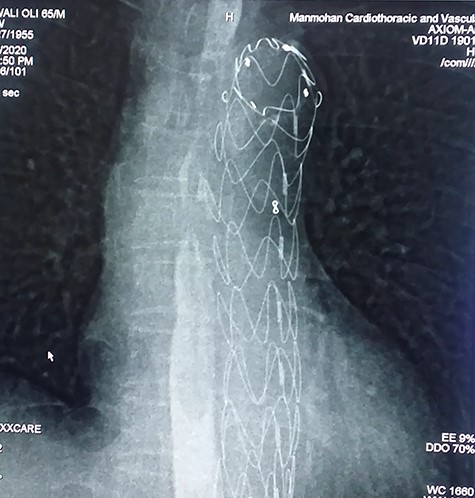

With the above findings, a diagnosis of ruptured descending thoracic aortic aneurysm with AEF was made. The patient was immediately taken for emergency TEVAR where 34 × 34 × 167-mm stent graft (Medtronic Inc. Valiant Thoracic Stent Graft) was deployed using a guidewire beyond the left subclavian artery till above the diaphragm via an incision over the left common femoral artery. Check angiogram showed no leak (Figs 4 and 5). Due to existing mediastinitis, feeding jejunostomy (FJ) was preferred over esophageal stenting. FJ was performed in the same setting after the endovascular procedure.

Post-operatively, she was continued on broad-spectrum antibiotics for mediastinitis with a gradual increase in FJ feed, which she tolerated well. She had an uneventful recovery and was discharged within a week following the procedure.